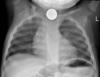

How is epiglottitis diagnosed and investigated?

ALWAYS SECURE AIRWAY FIRST * Keep calm with parent and i**ntubation equipment** should always be nearby * **Throat Swabs:** Both bacterial and viral swabs taken on intubation * **Blood Tests:** FBC, cultures and CRP (once airway secured) * **Lateral Neck X-Ray** 1) Thumb-Print Sign (swollen epiglottis) (5) 2) Thickened aryepiglottic folds 3) Increased opacity of the larynx and vocal cords X-Rays can help rule out epiglottitis if a normal epiglottis is visualised, but should not waste time in a critical situation